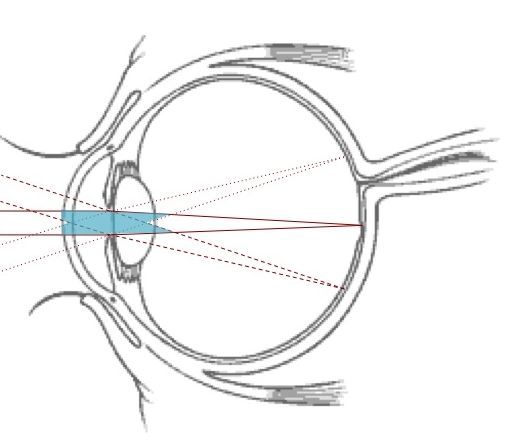

Let’s look at the cause of the field-of-view limitations in AO: wavefronts that are focused on different parts of the retina, cross different parts of the eye and thus incur different distortions. An AO correction that is valid along one direction is not valid along another direction. Assume that wavefront distortions are exclusively introduced at the entrance of the optical lens – this is the eye’s pupil, where wavefronts from all directions overlap. The distortions would then be the same whatever the field-direction. In this case the AO correction would be valid within large fields-of-view. In actuality, however, the distortions are introduced in at least 4 different planes: the front and back of the cornea and the front and back of the lens. Additional distortions are introduced by an index gradient within the optical lens. The temporal variations in these aberrations are caused by tear-film motions, blood pulsation and eye-movements. In multi-conjugate adaptive optics, deformable mirrors are optically conjugated to the planes where distortions are introduced. Each mirror corrects the distortions of its conjugate plane.

This requires knowledge of the distribution of optical index variations in the eye: a sensing stage is needed to tomographically reconstruct the profile of wavefront distortions. In a star-oriented multi-conjugate approach, wavefronts distortions are sensed along several directions. The tomographic reconstruction is done computationally and is only effective in those areas where at least two wavefronts overlap – the blue zone on Fig. 4. Outside that zone, the origin of distortions cannot be determined.

As the field-size increases, the zone where tomographic reconstruction is effective is reduced (see right panel on Fig. 4) and the quality of the correction therefore decreases.